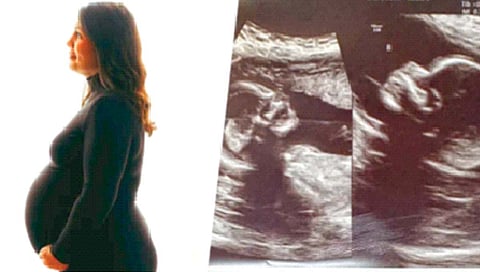

न्यूयॉर्क : संपूर्ण जगाला आश्चर्यात पाडणारा एक प्रकार अमेरिकेतून समोर आला आहे. अलाबामा या राज्यात हॅचर नावाची महिला गर्भवती असून या महिलेच्या पोटात दोन गर्भ आहेत. विशेष म्हणजे हे दोन्ही गर्भ वेगवेगळ्या गर्भाशयात आहेत. या दोन्ही बाळांना अन्न पुरवण्यासाठी दोन वेगवेगळे प्लॅसेन्टा (नाळ) आहेत. त्यामुळे या महिलेच्या पोटात असलेल्या बाळांना जुळे म्हणावे की काय? असा प्रश्न डॉक्टरांना पडला आहे. हॅचर सध्या 34 आठवड्यांच्या गरोदर आहेत.

वयाच्या 17 व्या वर्षी त्यांना ही बाब समजली. हॅचर यांना याआधी तीनवेळा गर्भधारणा झालेली असून त्यांना तीन मुले आहेत. या तिन्ही वेळा एखाद्या सामान्य महिलेप्रमाणेच त्यांना गर्भधारणा झालेली होती. यावेळी मात्र त्यांच्या पोटात दोन अर्भकं असून ती दोन्ही वेगवेगळ्या गर्भाशयात आहेत. त्यांची दोन मुलं प्रत्येकी सात, चार वर्षांची असून तिसरे मूल 23 महिन्यांचे आहे. चौथ्यांदा गरोदर राहिल्यानंतर हॅचर यांनी आठव्या आठवड्यात सोनोग्राफी केली, यावेळी त्यांच्या पोटात दोन अर्भकं असल्याचे डॉक्टरांना समजले. दरम्यान, हॅचर यांची प्रसूती त्यांच्या प्रकृतीसाठी धोकादायक ठरू शकते, असे म्हटले जात आहे. या जगात एका टक्क्यापेक्षाही कमी महिलांना दोन गर्भाशय असतात.